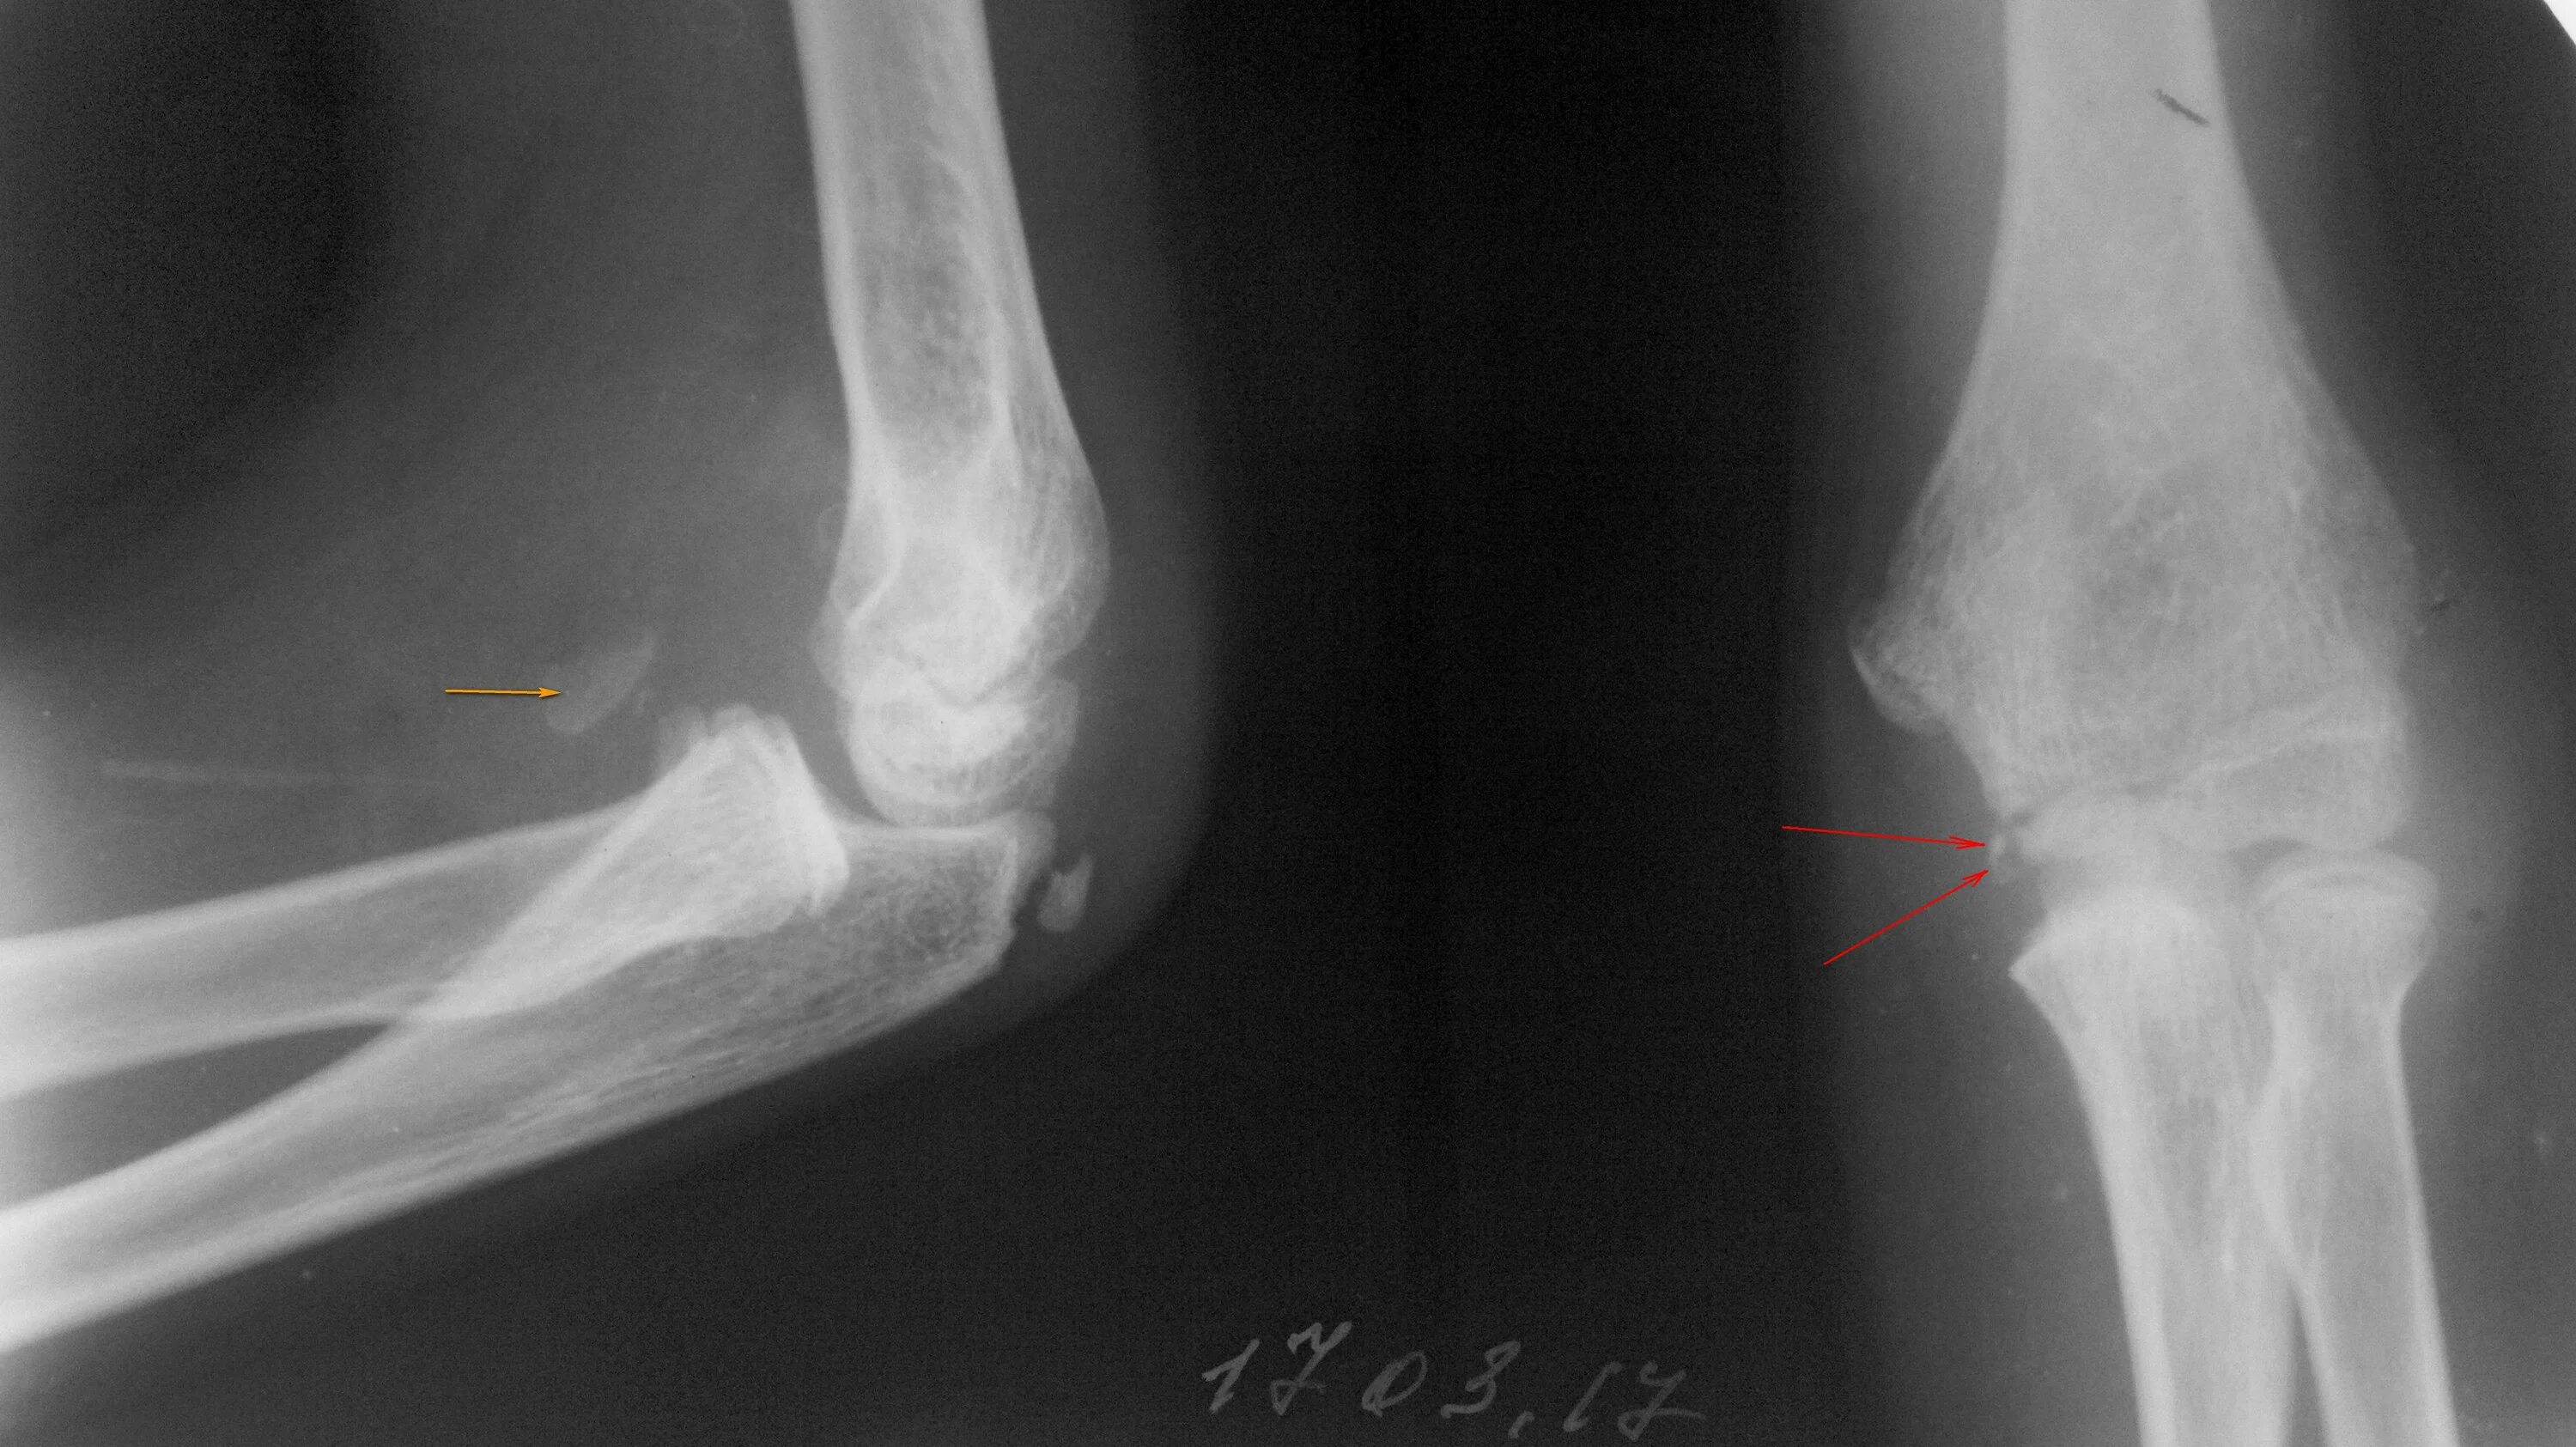

Перелом локтевой сустав мкб 10